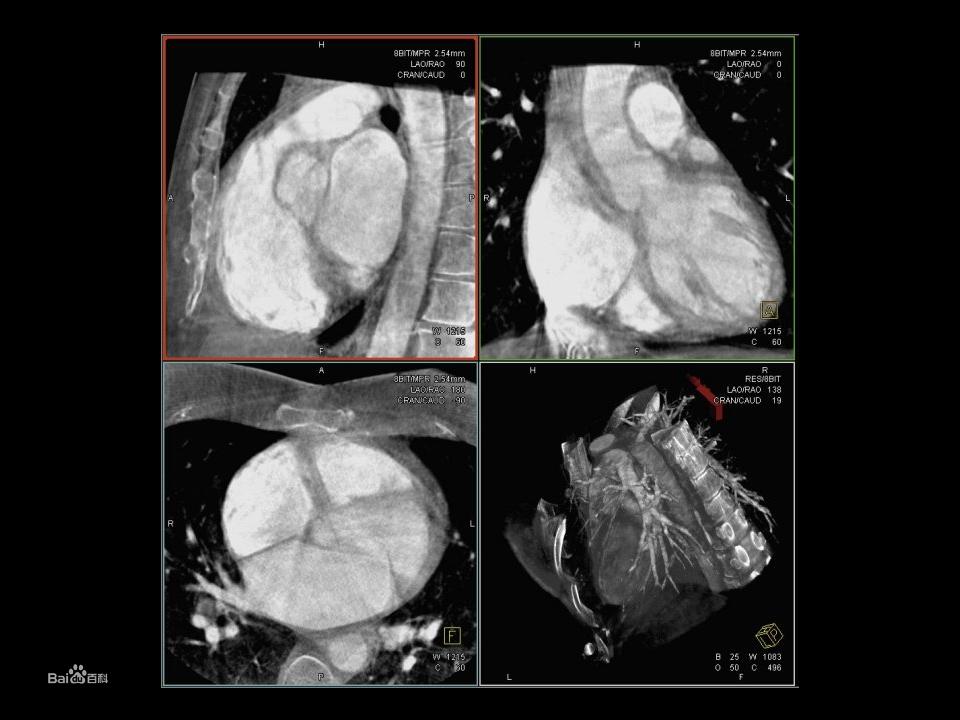

經導管的主動脈瓣植入術(TAVI)

TAVI複合手術經導管主動脈瓣植入需要精確定位主動脈根部來防止併發症的發生。良好的透視視圖 是必不可少的,由此,在確切的垂直於主動脈根部角度被認為是最佳的植入。最近,應用程式已經發布,支持外科醫生在選擇這個最佳的透視角度,甚至可以引導在C型臂自動投照引導瓣膜垂直至主動脈根部。有些方法是根據在手術前的CT圖像,其中用於分割的主動脈,並計算瓣膜植入的最佳角度。CT圖像必須與C-臂CT或透視圖像配準,並傳輸給血管造影系統。在配準過程中的錯誤,可能會導致在C型臂從最佳角度變化,必須手動修改。此外,術前CT圖像和手術時的解剖變異沒有說明。患者在做CT檢查時採取的是舉手位,但手術時雙手在其身體兩側,因此會導致偏差。基於這樣一個進展,外科醫生不依賴於手術前由放射科採集CT圖像,這樣就簡化了手術室的工作流程,並減少過程中的錯誤。